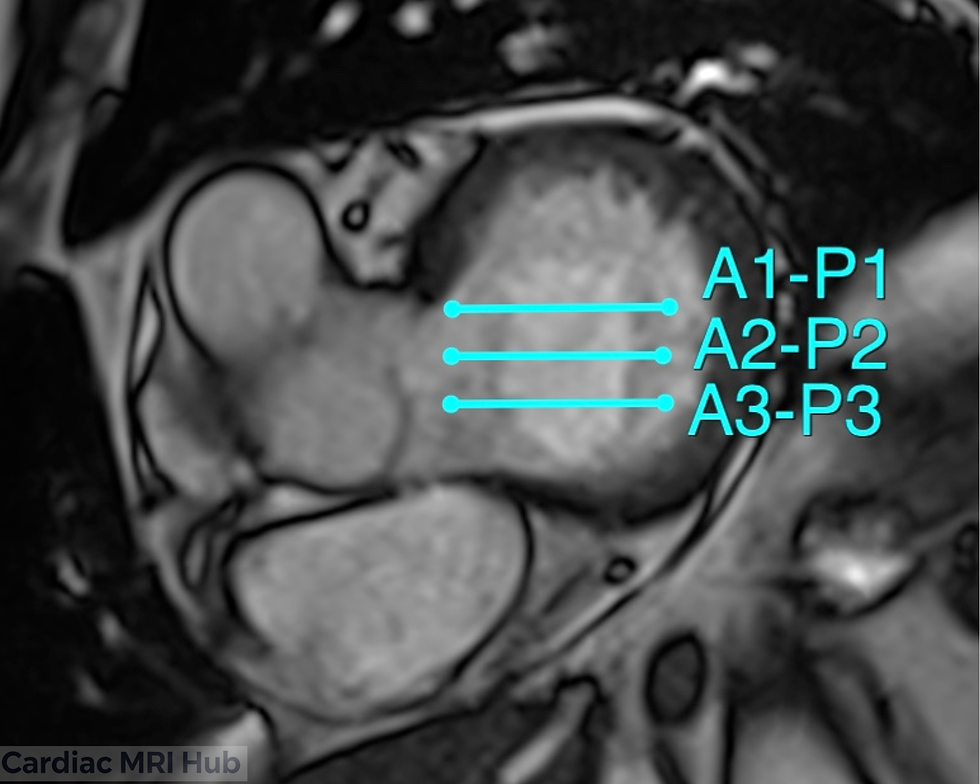

The mitral valve scallops view is an essential imaging technique in cardiac MRI that provides detailed visualization of the mitral valve's complex anatomy. Using the Carpentier classification system, the mitral valve is divided into six distinct segments or scallops, three anterior (A1, A2, A3) and three posterior (P1, P2, P3) which allows for precise localization of valvular pathology. This imaging approach is particularly valuable for evaluating mitral valve prolapse, regurgitation, and structural abnormalities, making it crucial for pre-surgical planning and guiding interventional procedures. By systematically imaging each scallop segment, technologists can provide clinicians with comprehensive information about leaflet motion, coaptation defects, and chordal apparatus integrity.

Scallop Segmentation: Systematic evaluation of each individual scallop (A1, A2, A3, P1, P2, P3) to precisely localize areas of prolapse, restricted motion, or perforation using the Carpentier classification.